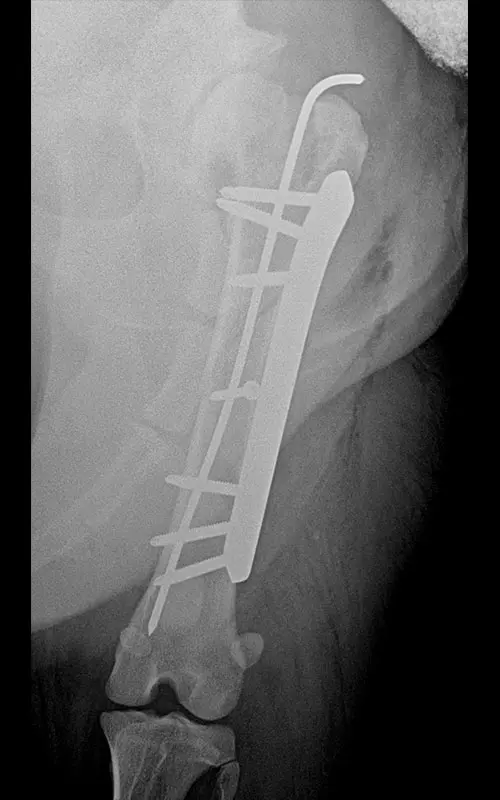

Combination of polyaxial locking plating and medullary pinning to treat multiple unstable fractures

It is a common case where long tubular bones suffer multiple fractures and there is no bone lying on top of each other after repositioning that would aid in stability after fixation. The K-wire-and-plate combination already known during DCP plating can also be used for locking plating:

- Among locking systems, only the polyaxial system is fully suitable for this task, because during the insertion of srews the medullary nail can be bypassed (cf. in monoaxial systems, if the nail is under the plate hole, no screw can be inserted in that hole).

In our case, a 10-year-old labrador is involved in a car accident and his left femur and right tibia are severely injured. The dog had difficulty moving anyway due to severe hip arthrosis. During one surgical narcosis, K-pin - polyaxial locking plating was applied to both bones, the larger fragments were also fixed with 1-1 lag screws.